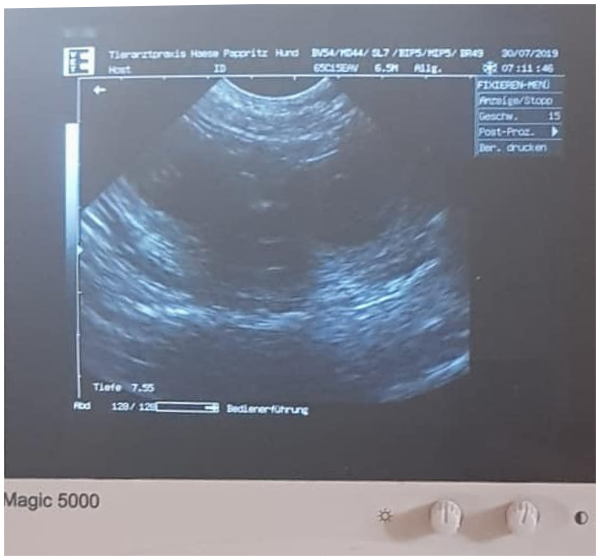

Unsere Gwendolin vom Rittergut wurde am 6. u. 7. Juli 2019 von Cid pod Svatou Horou gedeckt. Werte der Verpaarung: IK 0,00 und AVK 98,39

30. Juli 2019